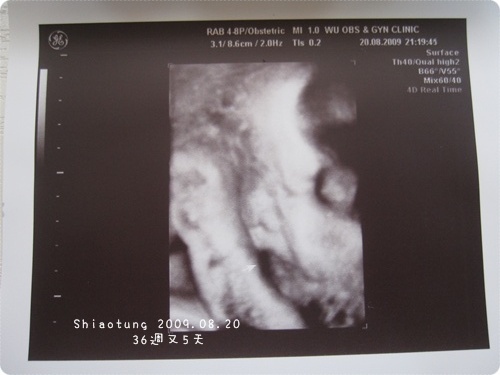

這套房還真是很擠了。

擠的臉都看不清楚,

乾脆跟醫生說拍拍腳好了!

看得出來嗎?

一隻大腳就踩著我的肺或是胃、甚至是肋骨?

頂天的彷彿想要往上踢。

腳趾三不五時會跟靓一樣的用力縮放...

4D照片一看到,

我跟老公、醫生都驚呼:好胖喔!